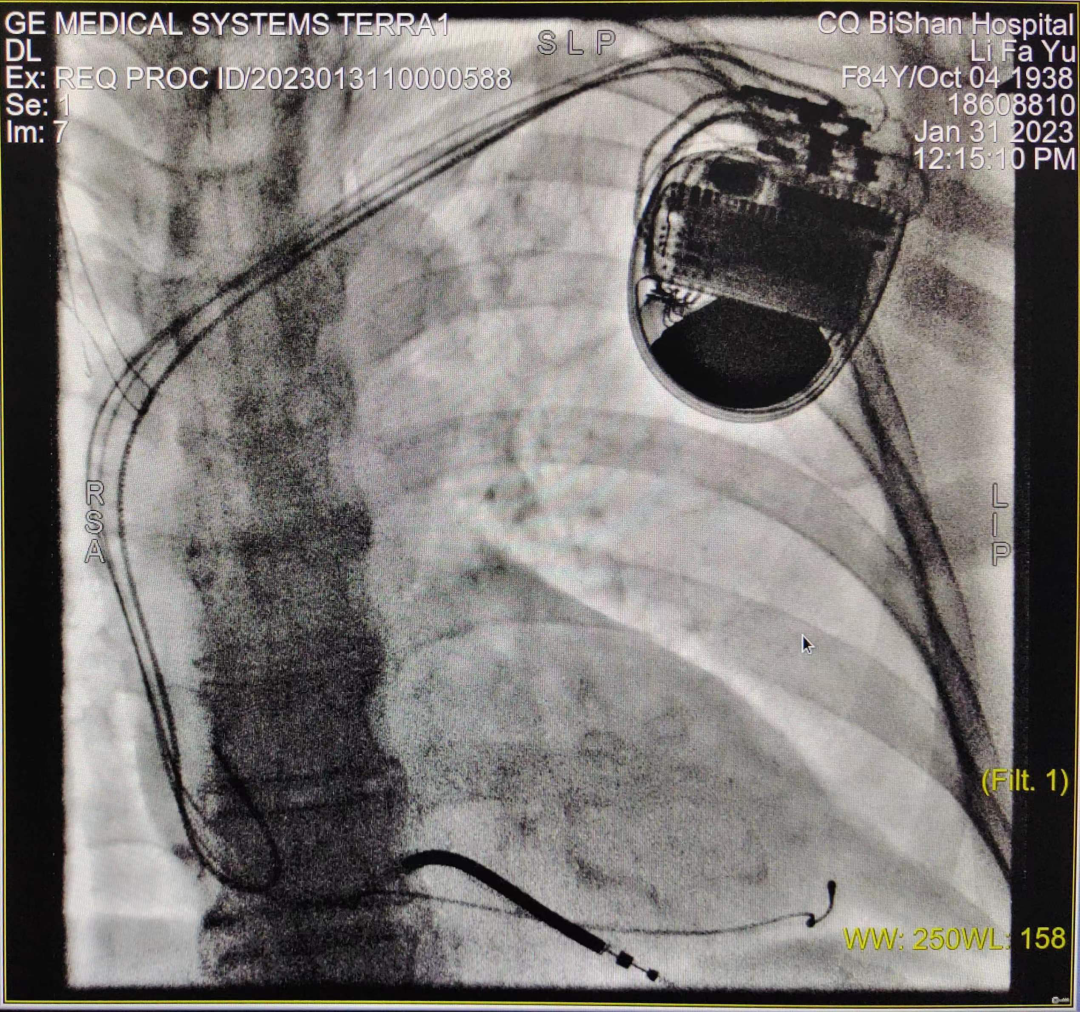

CRT-D植入术进行中

于长青主任高度重视,结合患者既往病史、治疗史,先后多次组织科室团队及医院MDT团队讨论,并报请医务科批示,最终决定给该患者安置三腔起搏器,实施双心室同步起搏的心脏再同步化治疗,改善患者的心力衰竭症状。科室起搏电生理团队经过充分的术前准备,于1月31日成功为患者实施CRT-D介入手术,手术过程顺利,患者无任何不适,术后5天即安全出院。术后心电图提示:窦性心律,双心室起搏心律,QRS宽度120-130ms,患者劳累气促症状较前明显改善。